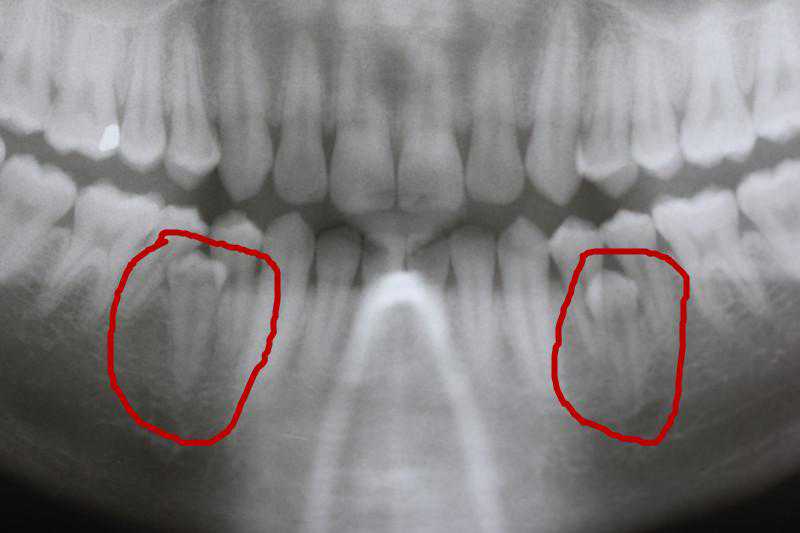

齿我妹妹的上门牙最近总是疼,去医院拍了个牙片,竟然发现在两颗门牙之间还有一颗牙齿。从外表根本看不出来,是在骨头里面埋着的。(图123)

牙有的多生牙先于所在部位恒牙的萌出,故而影响了恒牙的正常萌出和排列,患儿的家长误以为是恒牙萌出,并没有引起重视,待发现时已经错过最佳的治疗时机,拔除多生牙后再配合牙齿矫正才可将牙齿排齐;也有的多生牙和恒牙同时萌出,造成恒牙萌出位置偏斜、牙列拥挤等问题;个别多生牙由于埋伏位置过深或倒置,无法萌出,不易被察觉。(图4)

牙无法萌出的多生牙又分两类。一类是可以和我们“和平共处”,大家相安无事;另一类是由于某些原因导致多生牙发生移动,造成附近牙齿的损伤或者其继发囊肿,造成周围组织的破坏,对于这类一定要进行处理,否则破坏会继续增大。(图5)